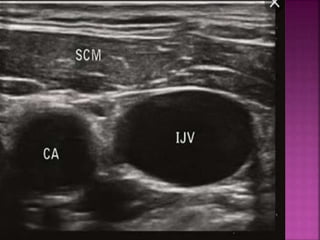

 Use ultrasound for cannulation

 Place inright internal jugular  Use ultrasound for cannulation  Use fluroscopy for placement  Place tip well within atrium